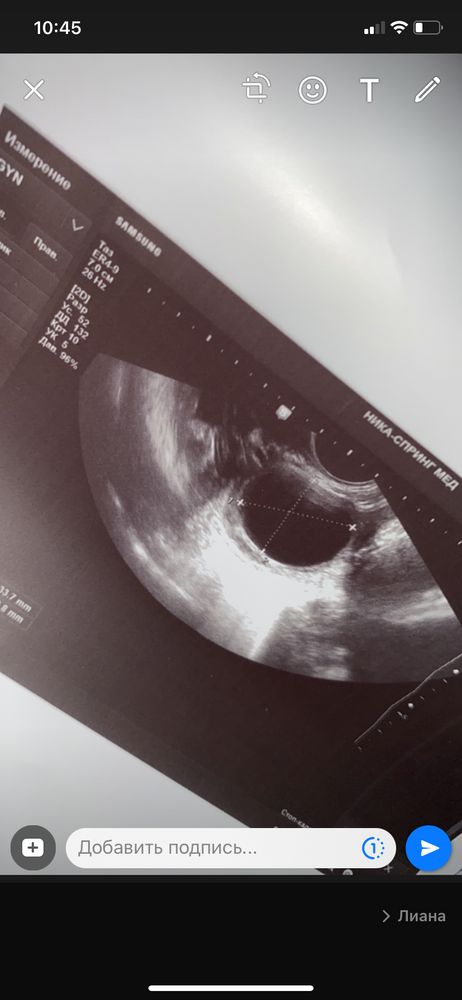

вот такой был

У меня такая была.